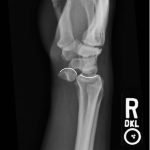

Plain film of the right wrist showed the classic “spilled teacup” consistent with a lunate dislocation. There is a loss of the normal articulation between the distal radius and lunate (white curved highlights represent expected points of articulation).

The most common mechanism leading to a dislocation of lunate is a fall onto an outstretched hand with the wrist in extension. Damage to the ligamentous infrastructure (commonly the dorsal radiolunate ligament) causes destabilization.1 Lunate dislocations are distinguished from perilunate dislocations by assessing for the preservation of the articulation between the lunate and distal radius. In lunate dislocations, this articulation is disrupted leading to the classic “spilled teacup” appearance as seen above. However, if the articulation between the distal radius and lunate is preserved, but there is displacement of the carpal bones (eg, scaphoid, triquetrum, etc), then the dislocation is referred to as a perilunate dislocation.

Plain film radiography oriented in the lateral view is typically the first-line modality for diagnosis. However, advanced imaging such as computed tomography or magnetic resonance imaging may be required to rule out fracture.